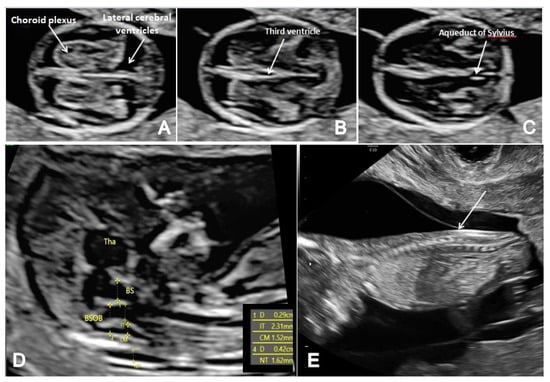

Figure 1.

The FTAS protocol for CNS evaluation: (A) transverse view of the brain showing the contour and shape of the fetal skull, choroid plexus (arrow) and the filling of lateral cerebral ventricles (arrow); (B,C) further evaluation of the cerebral ventricular system, in transverse planes of the brain showing the third ventricle (B) and aqueduct of Sylvius (C) (arrow); (D) mid-sagittal view of the brain showing the thalamus (Tha) and the measurements for the brain stem (BS), the fourth ventricle (IT), cisterna magna (CM), the nuchal translucency (NT) and the brain stem–occipital bone ratio (BSOB); (E) longitudinal view of the spine regularity and underlying skin (arrow).

In terms of FTAS, we adopted a standard protocol that added the guidelines for basic FT screening [8] and several features for a more detailed structural assessment at this gestational age. The detailed scanning protocol included two axial planes of the brain (at the level of the choroid plexus and third ventricle and the level of the cerebral peduncles and aqueduct of Sylvius) and the sagittal view of the fetal face for the evaluation of the posterior brain complex. The scanning protocol aimed to assess the contour and shape of the fetal skull, the choroid plexus shape and relative filling of the ventricles and the aspect of the lateral cerebral ventricles (Figure 1A). We noted the presence of the third ventricle (Figure 1B) and the aspect and position of AS (Figure 1C), the presence of the CM and the fourth ventricle (the anechogenic area between the posterior border of the brain stem (BS) anteriorly and the choroid plexus of the fourth ventricle posteriorly) (IT) [13]. We investigated the presence of posterior and caudal displacement of the mesencephalon by searching for the ‘crash’ sign in the thalamic axial plane [14]. The BS/BSOB ratio was subjectively evaluated and measured when it appeared abnormal [15], and the presence of CM was noted (Figure 1D). Fronto-maxillary angle was measured in all cases, as part of the genetic screening, but narrow-angle cases were suspected also for neural tube defects [16]. In all cases, the spine was also evaluated in two-dimensional (2D) longitudinal planes, recording its regularity and the continuity of the underlying skin layer (Figure 1E).